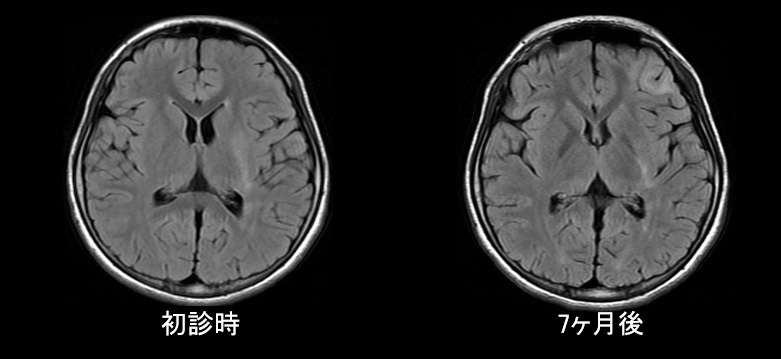

• 左基底核のT2WI/FLAIRでの高信号、ADC上昇

• 経過中に左前頭葉にT2WI/FLAIR高信号域が出現、左基底核が萎縮

経過1

入院後脳波:発作時、左前頭極部から律動性徐波が出現し、対側へ伝播し広範化する。

薬物療法で発作頻度が減少した時期もあったが、意識減損発作や右上下肢の間代性痙攣等を繰り返していた。

初診から3ヶ月後に髄液GluR抗体陽性が判明した。